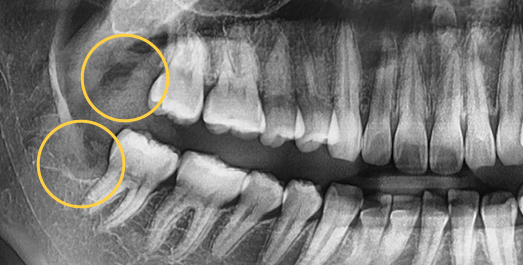

Some wisdom teeth erupt normally, but others may erupt at an angle, horizontally, or remain fully impacted. Wisdom teeth that do not erupt properly can disturb the dental arch and are difficult to clean, which may lead to decay of adjacent molars. In such cases, extraction is recommended.

• Horizontally

impacted wisdom tooth

• Angulated

• Vertically